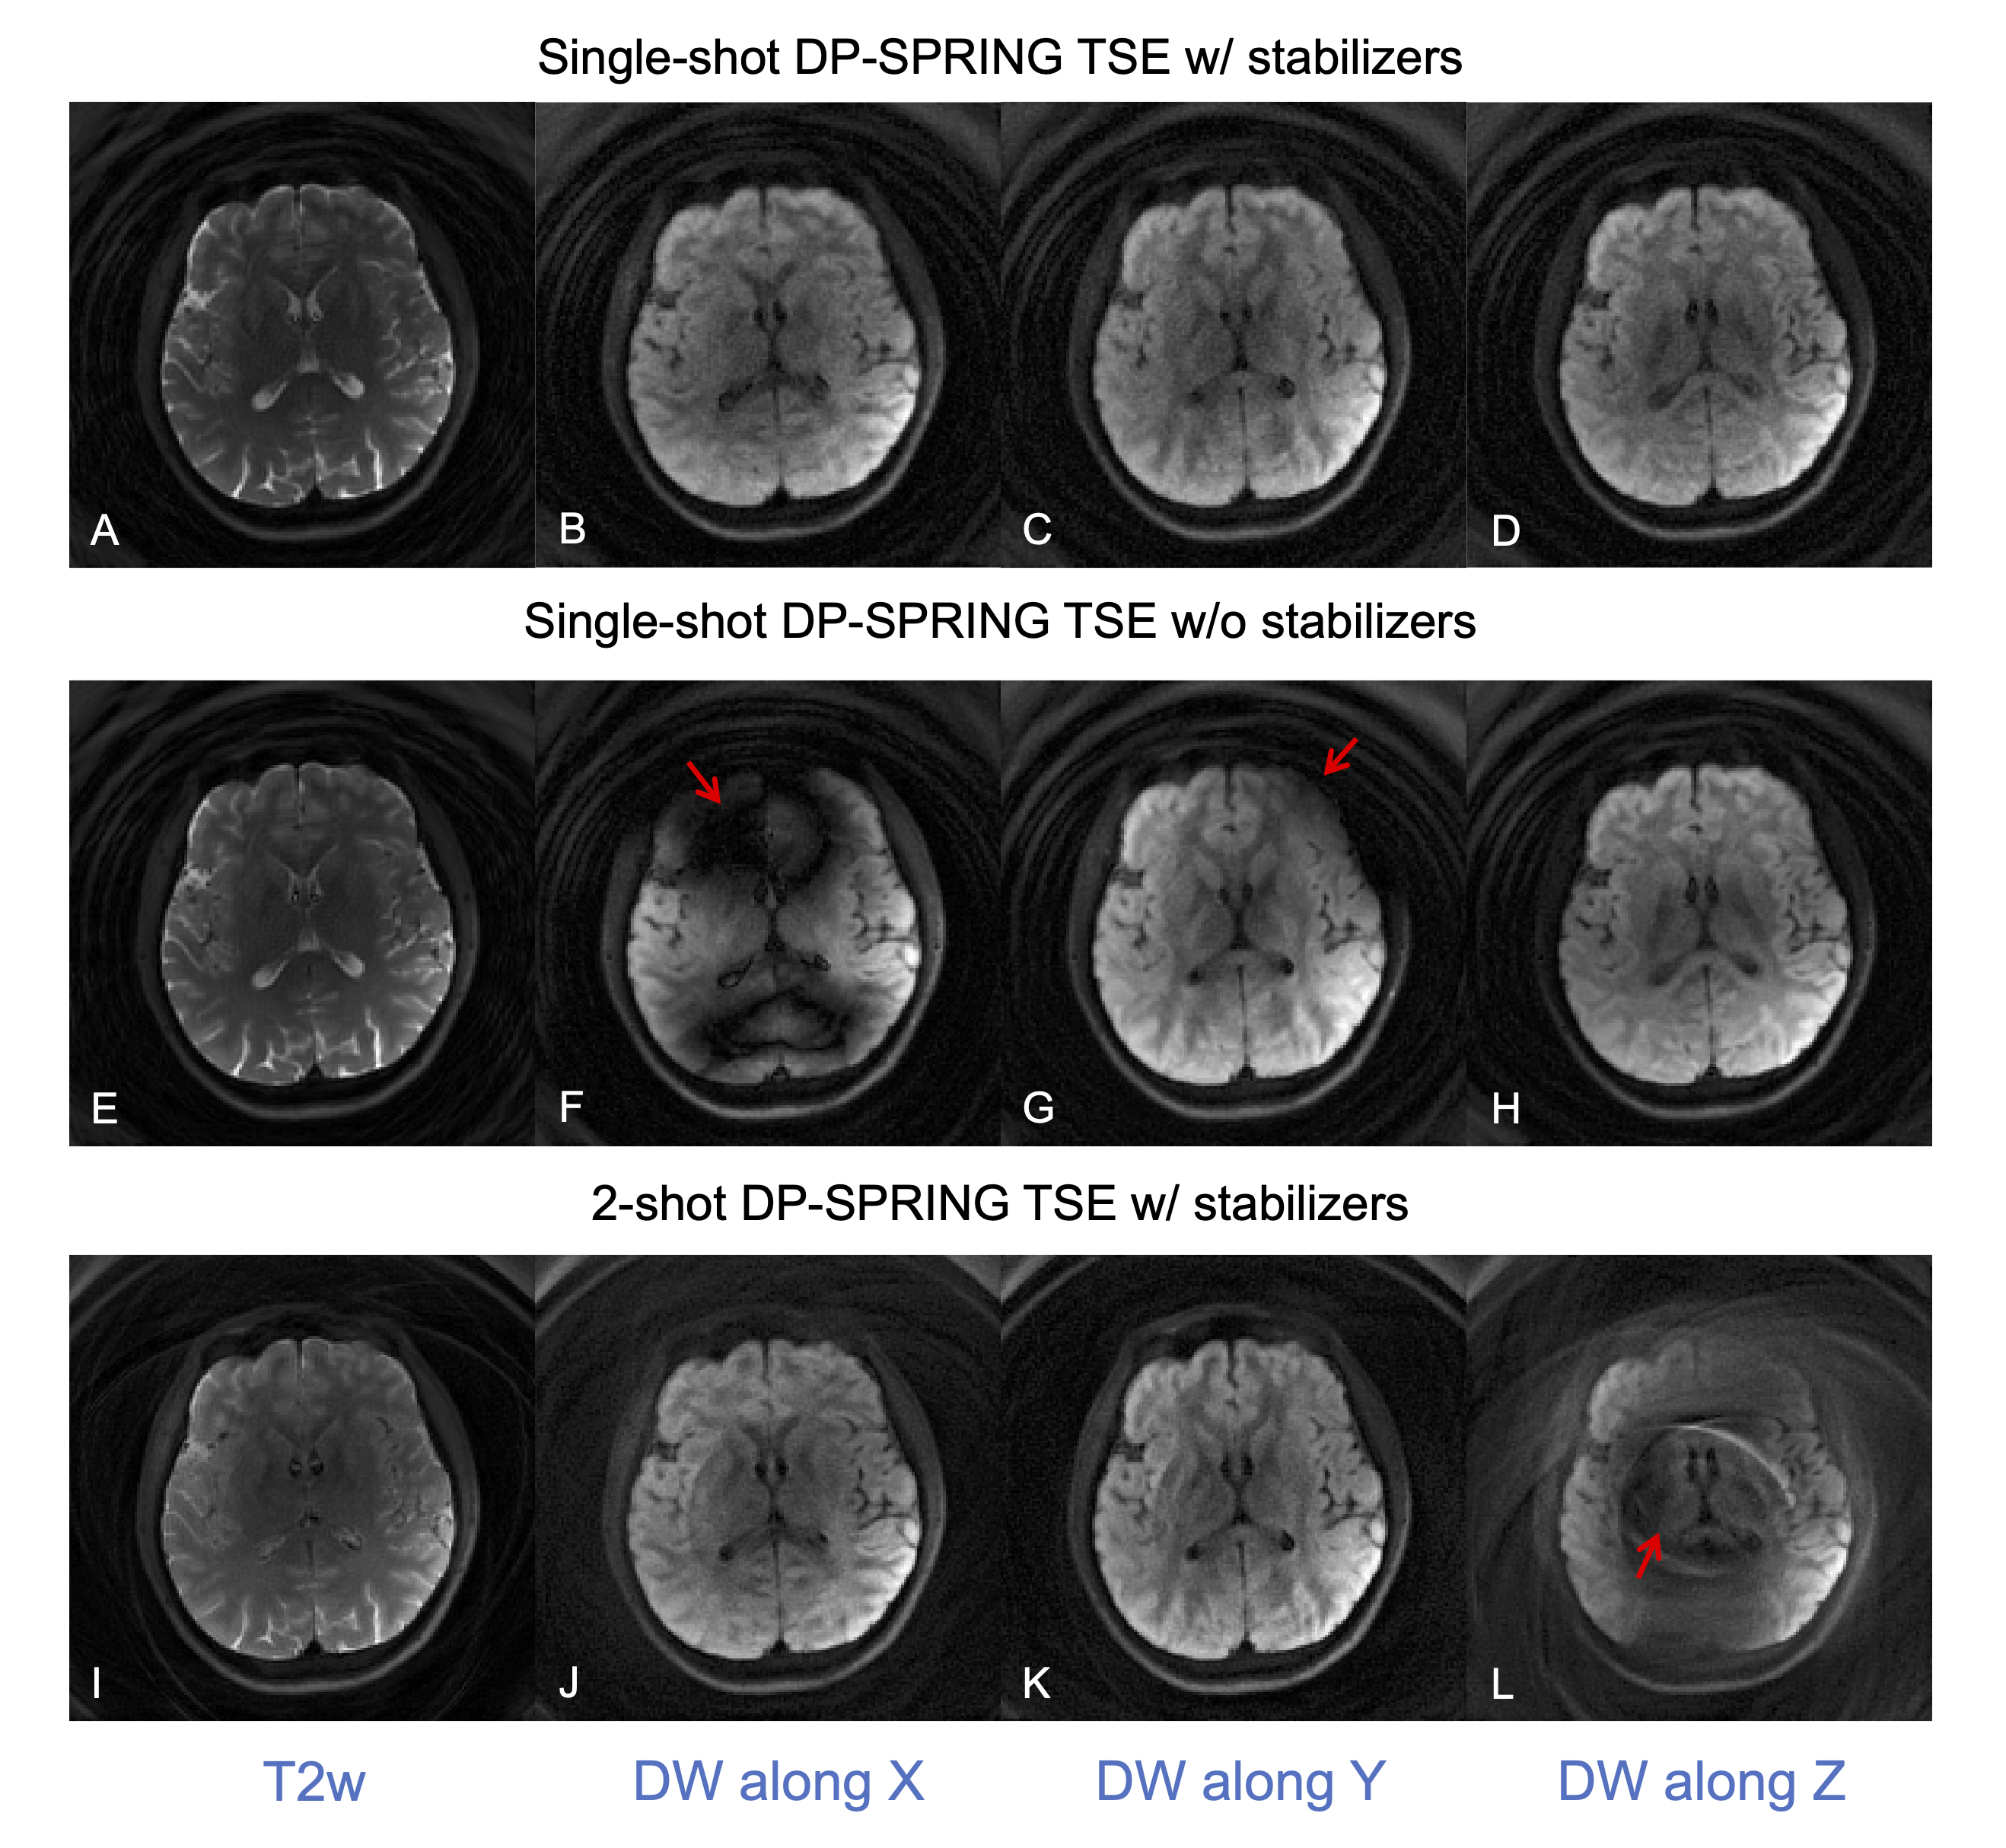

Figure 3 demonstrates the performance improvement for the proposed SS-DP-SPRING TSE with magnitude stabilizers (top) compared to that without stabilizers (middle) and for 2-shot DP-SPRING TSE with stabilizers (bottom). All images were reconstructed using NUFFT. Unpredictable severe bands of signal loss can be seen in Figure 3F-G from SS-DP-SPRING TSE without stabilizers when the diffusion gradient is on. When using 2-shot acquisition, artifacts and signal cancellation are obvious as shown in Figure 3L, because of cardiac pulsation, when the diffusion gradient is along head-foot direction. Image degradation attributed to magnitude or phase modulation is substantially reduced when applying stabilizers along with the single-shot theme.

Figure 3. In vivo brain images showing the stability of image quality from the proposed single-shot DP-SRPING TSE sequence with magnitude stabilizers (A-D) over single-shot DP-SRPING TSE without stabilizers (E-H) and a 2-shot DP-SRPING TSE sequence with stabilizers (I-L). Note that all images were reconstructed via NUFFT, and images E-H have theoretical 2X SNR higher than other images. (NSA = 1).